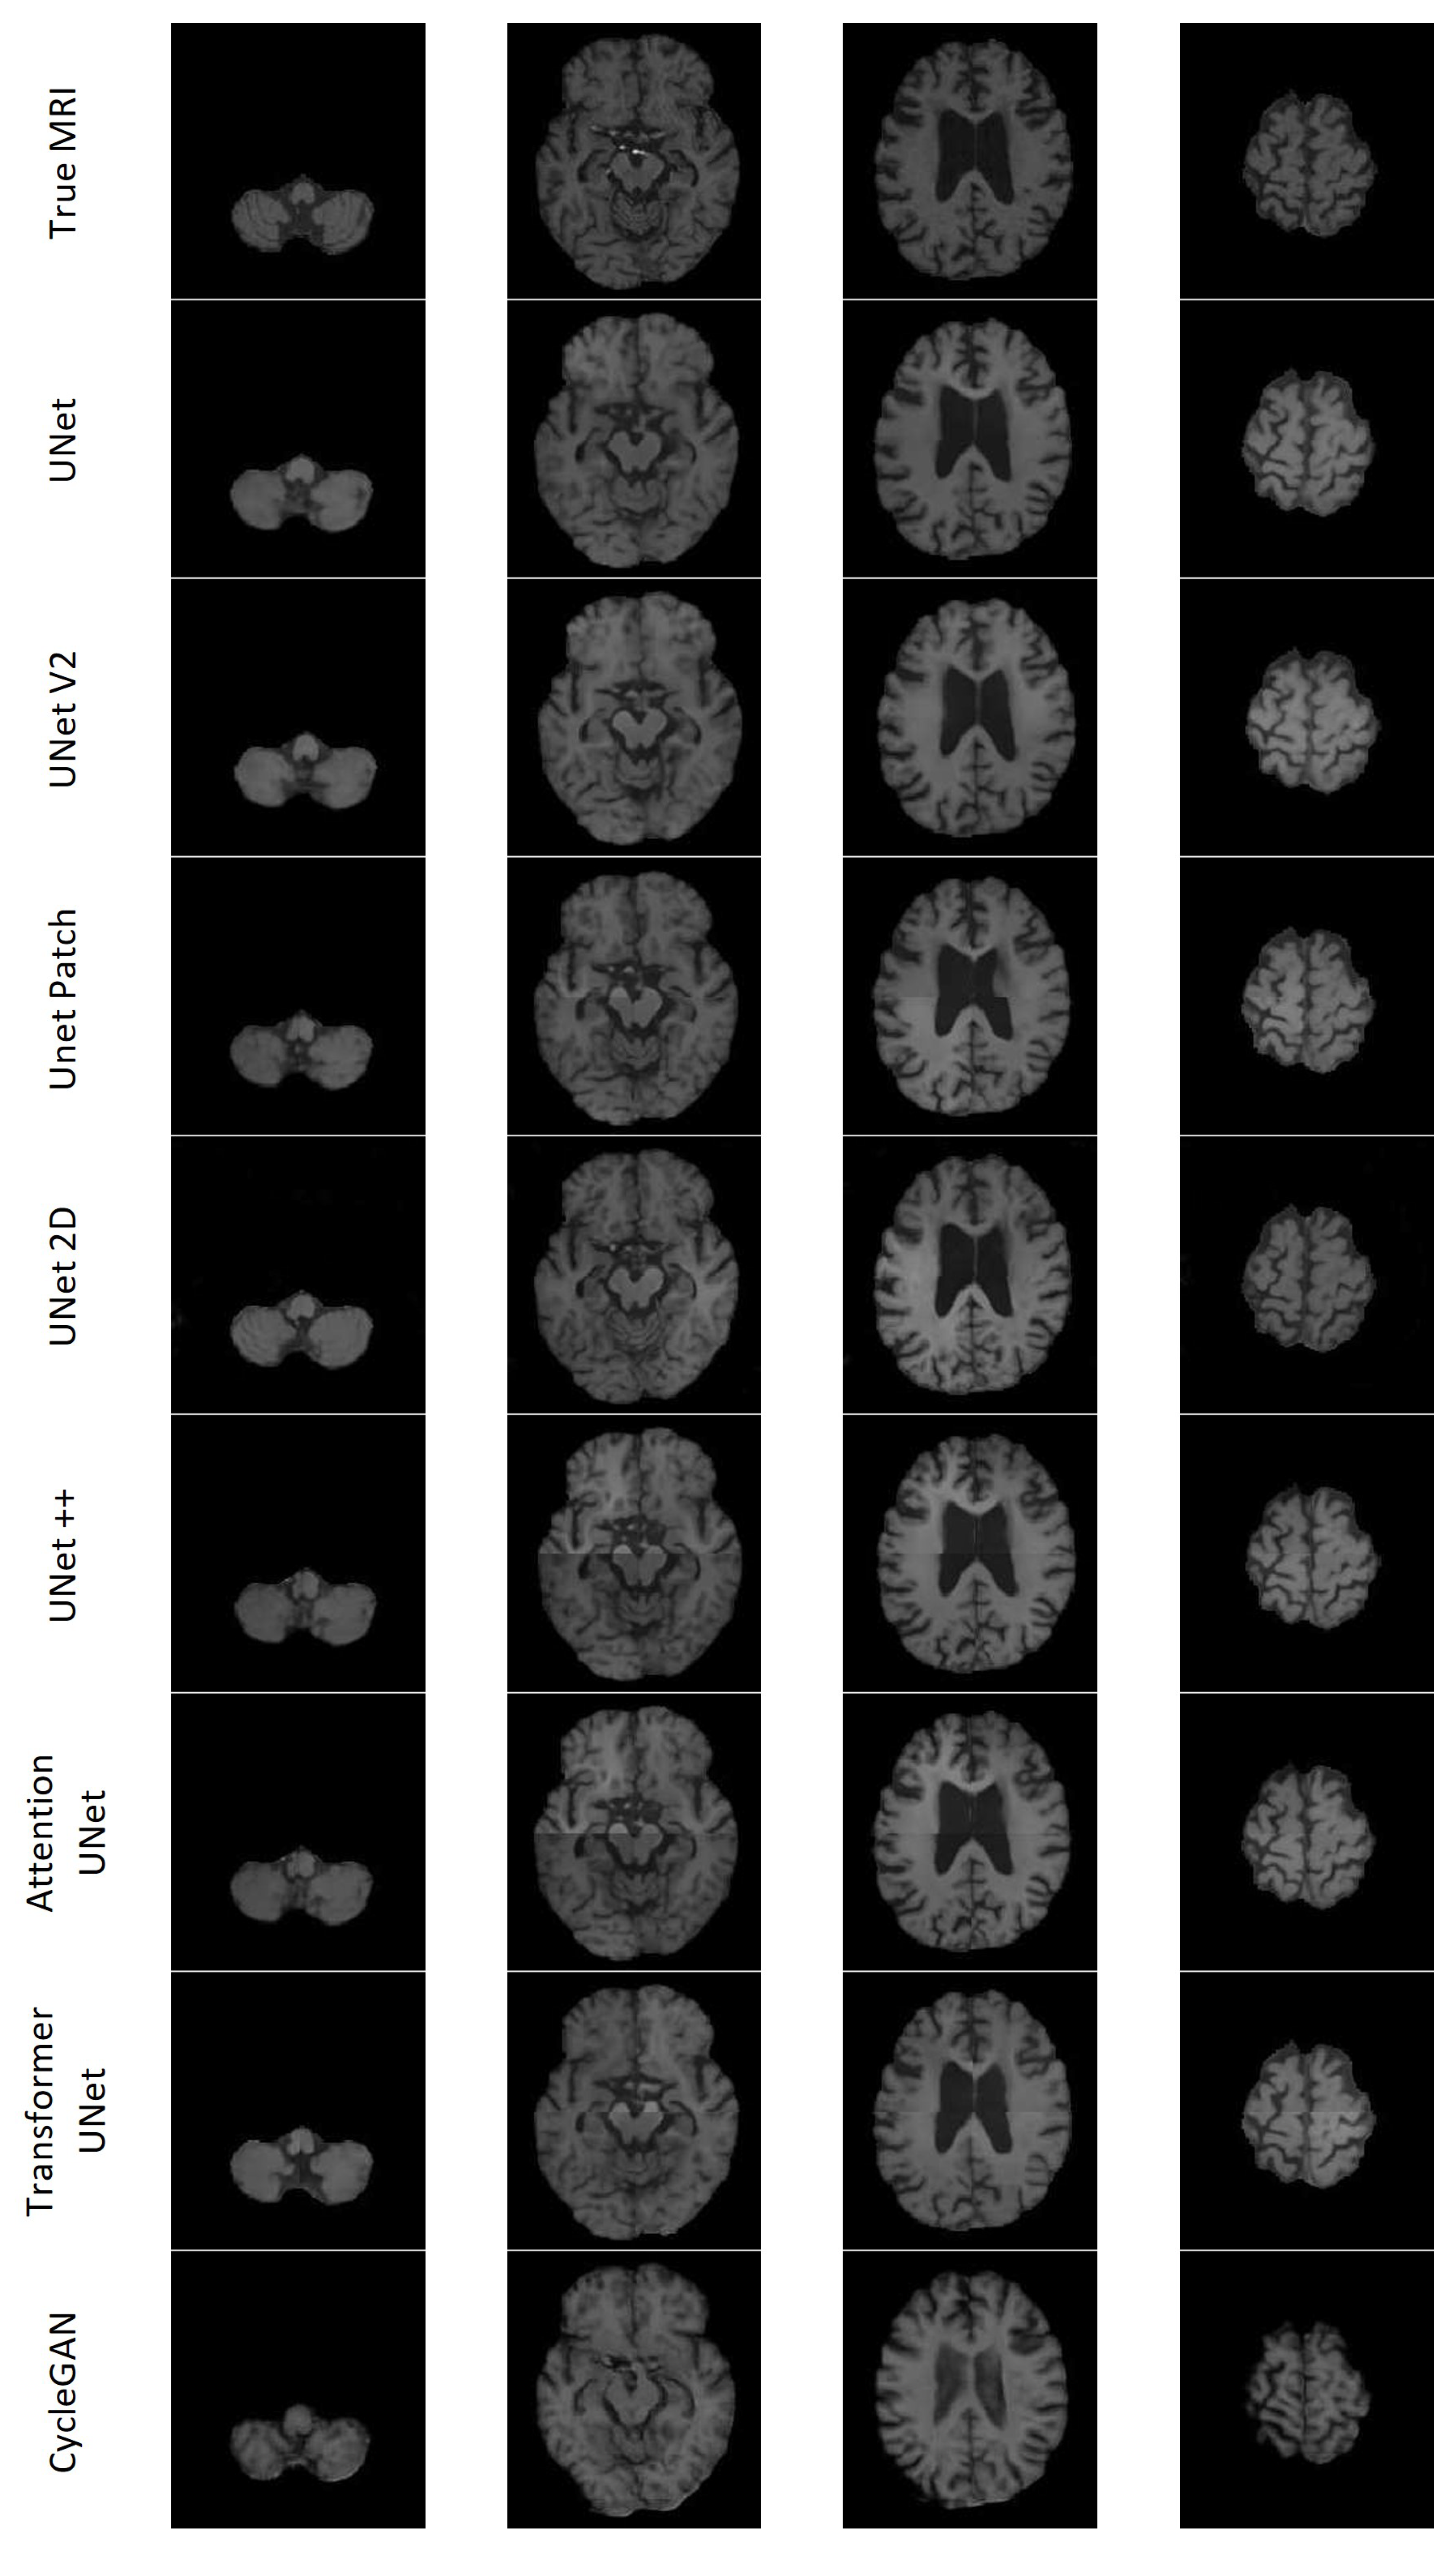

All the models except UNet++ and Attention UNet clearly depict the lesion for Patient A; however, most of the lesions in the synthesised MRIs lacked contrast. CycleGAN appeared to have the least contrast between the lesion and surrounding area. Transformer UNet exhibited considerably higher contrast for the lesion; however, it failed to accurately capture the lesion’s boundary. 2D UNet gave rise to a mottled effect over the lesion area. Patient C presented with a notably large lesion; however, only UNet V2 and 2D UNet managed to retain any indication of the lesion. Nevertheless, the presence of the lesion remains subject to debate in both cases. The models encountered difficulties in accurately reproducing other features of Patient C’s dataset. Additionally, with the exception of CycleGAN, they lacked the necessary contrast between the various types of brain tissue. The inability to generate sufficient contrast was observed across multiple synthetic MRIs, particularly in cases where the true MRI exhibited lower levels of contrast. CycleGAN demonstrated good contrast across all synthetic MRIs; however, it often failed to replicate the brain structures found on the true MRI. Specifically, CycleGAN seemed to have learned the presence of sulci along the brain’s edge, but generated them in a semi-random manner rather than reproducing the patterns observed in the CT. The 2D UNet model exhibited notable accuracy in modelling gyri and sulci in the synthesised MRI, displaying good contrast. On the other hand, the patch-based models faced challenges in accurately predicting the edges of the patches, resulting in misalignment issues. Figure 20 shows seven axial slices of the true MRI and the synthetic MRIs from each of the eight models for Patient D.

Figure 20. Four slices of an MRI of Patient D generated by each of the eight models along with the True MRI.